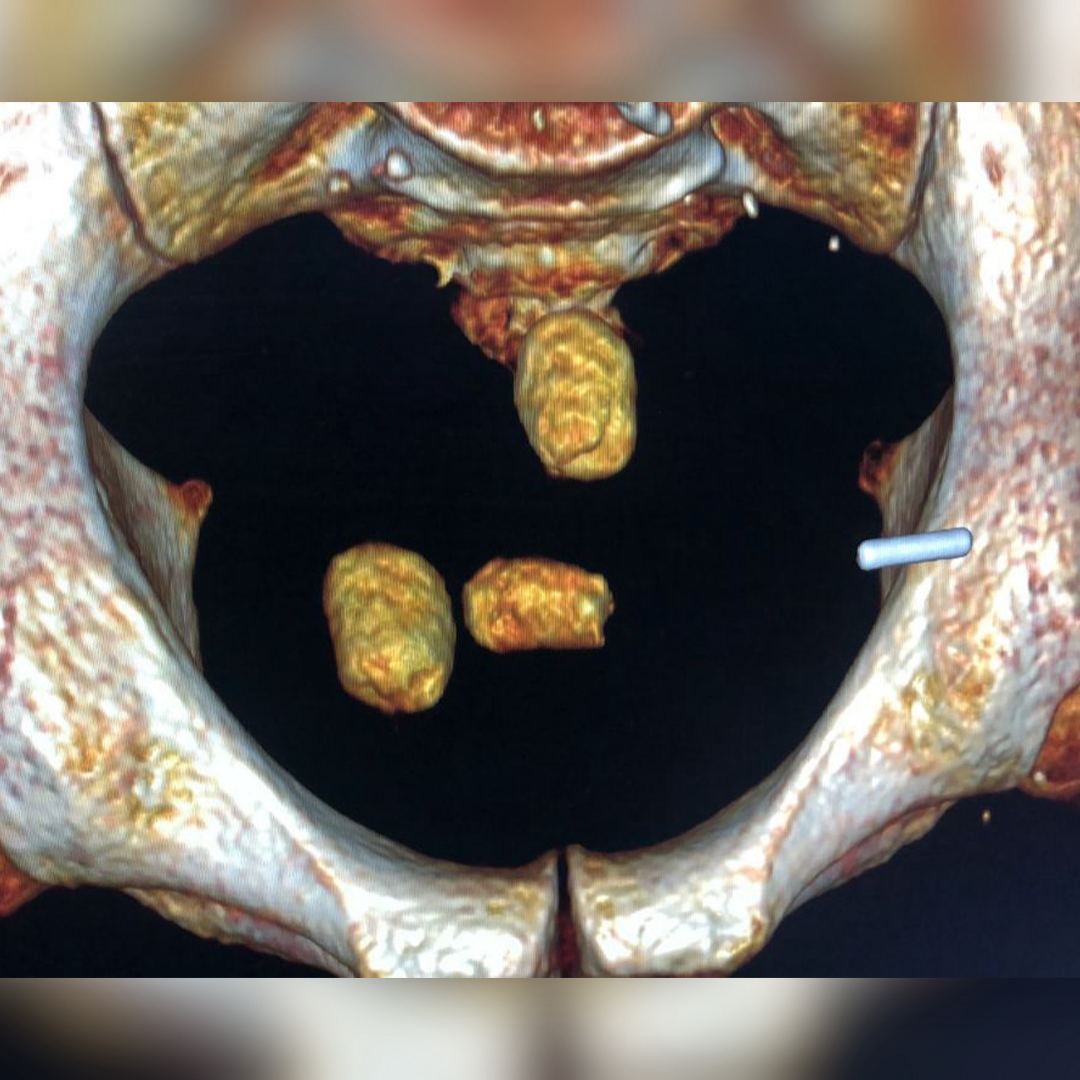

КНБ задержал наркокурьеров-"глотателей" в аэропорту Актау

Общий вес изъятых веществ составил около 1 кг.

Комитет национальной безопасности пресек контрабандный канал поставки наркотиков в Казахстан, передает Caravan.kz со ссылкой на пресс-службу ведомства.

21 февраля в международном аэропорту Актау оперативниками ДКНБ по Мангистауской области и пограничниками во взаимодействии с сотрудниками ДЭР по подозрению в транспортировке наркотиков задержаны два иностранных гражданина.

Рентгеноскопическое исследование показало наличие в их брюшной полости посторонних предметов. Медицинскими процедурами из желудков иностранцев извлечено свыше 30 контейнеров, которые содержали героин и синтетические наркотики.

Фигурантам избрана мера пресечения в виде содержания под стражей. Проводится досудебное расследование по части 4 статьи 286 УК РК.